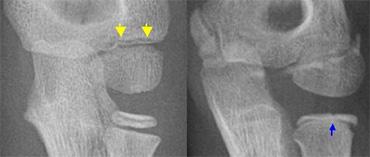

LEFT a subtle lateral condyle fracture. Less than 2 mm displacement and probably stable. RIGHT a different case. Oblique view gives nice impression of fracture. Blue arrow indicates a cleft epiphysis of the radius (normal variant)

Gãy lồi cầu ngoài (5)

Trong gãy lồi cầu ngoài, đường gãy thực sự có thể rất khó nhận thấy vì mảnh xương vùng hành xương có thể rất nhỏ.

Mảnh gãy thường bị xoay.

Tư thế chụp chếch có thể hữu ích, nhưng thường không được thực hiện thường quy (hình).